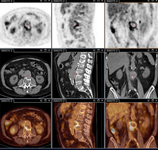

Aneurisma micótico na aorta torácica da febre Q diagnosticado na PET: PET/TC com 18-fluordesoxiglucose. Neste paciente assintomático com história de valva cardíaca e sorologia elevada, a PET permitiu diagnosticar endocardite aórtica na valva nativa com aneurismas micóticos da aorta torácica e lombar

Institut Hospitalo-Universitaire Méditerranée Infection (obtido consentimento do paciente)

Endocardite por febre Q diagnosticada na PET: PET/TC com 18-fluordesoxiglucose. Neste paciente assintomático com história de valva cardíaca e sorologia elevada, a PET permitiu diagnosticar endocardite aórtica na valva nativa com aneurismas micóticos da aorta torácica e lombar

Aneurisma micótico na aorta lombar da febre Q diagnosticado na PET: PET/TC com 18-fluordesoxiglucose. Neste paciente assintomático com história de valva cardíaca e sorologia elevada, a PET permitiu diagnosticar endocardite aórtica na valva nativa com aneurismas micóticos da aorta torácica e lombar